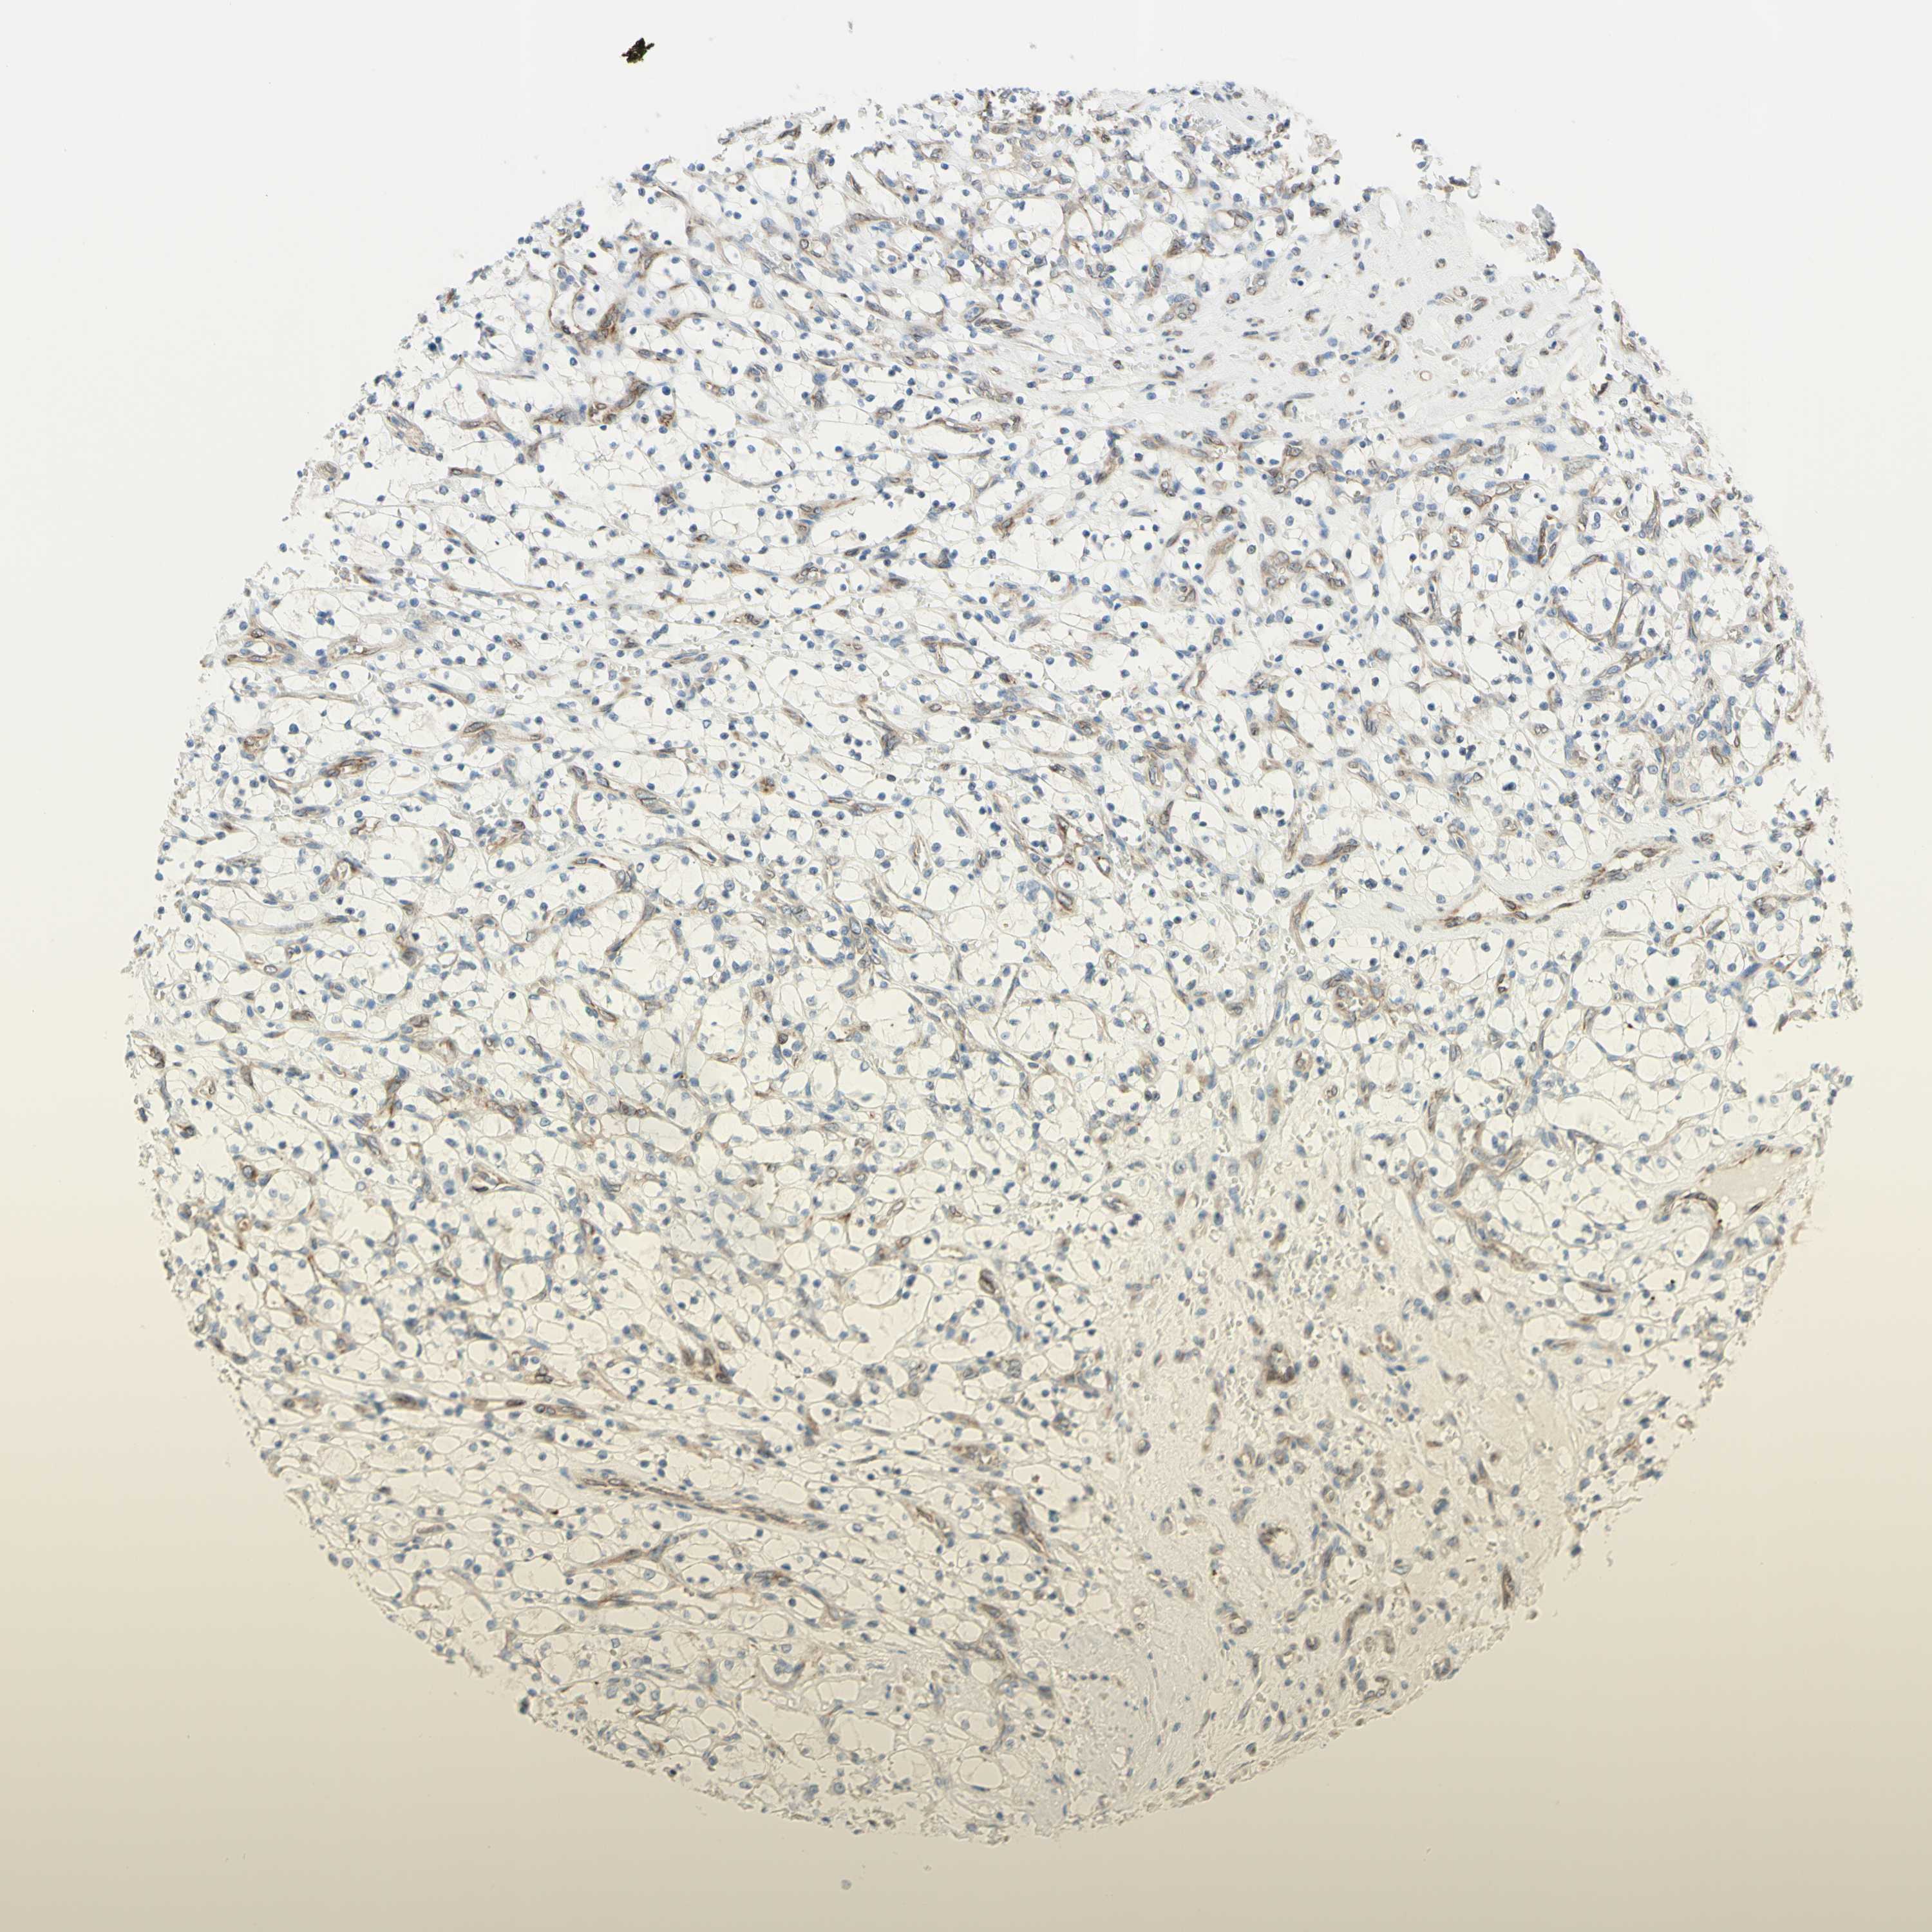

KIDNEY RENAL CLEAR CELL CARCINOMA (VALIDATION) - Interactive survival scatter ploti

TRAF2 is not prognostic in Kidney Renal Clear Cell Carcinoma (validation)

: 13.68

Average pTPM 17.4

Number of samples 100